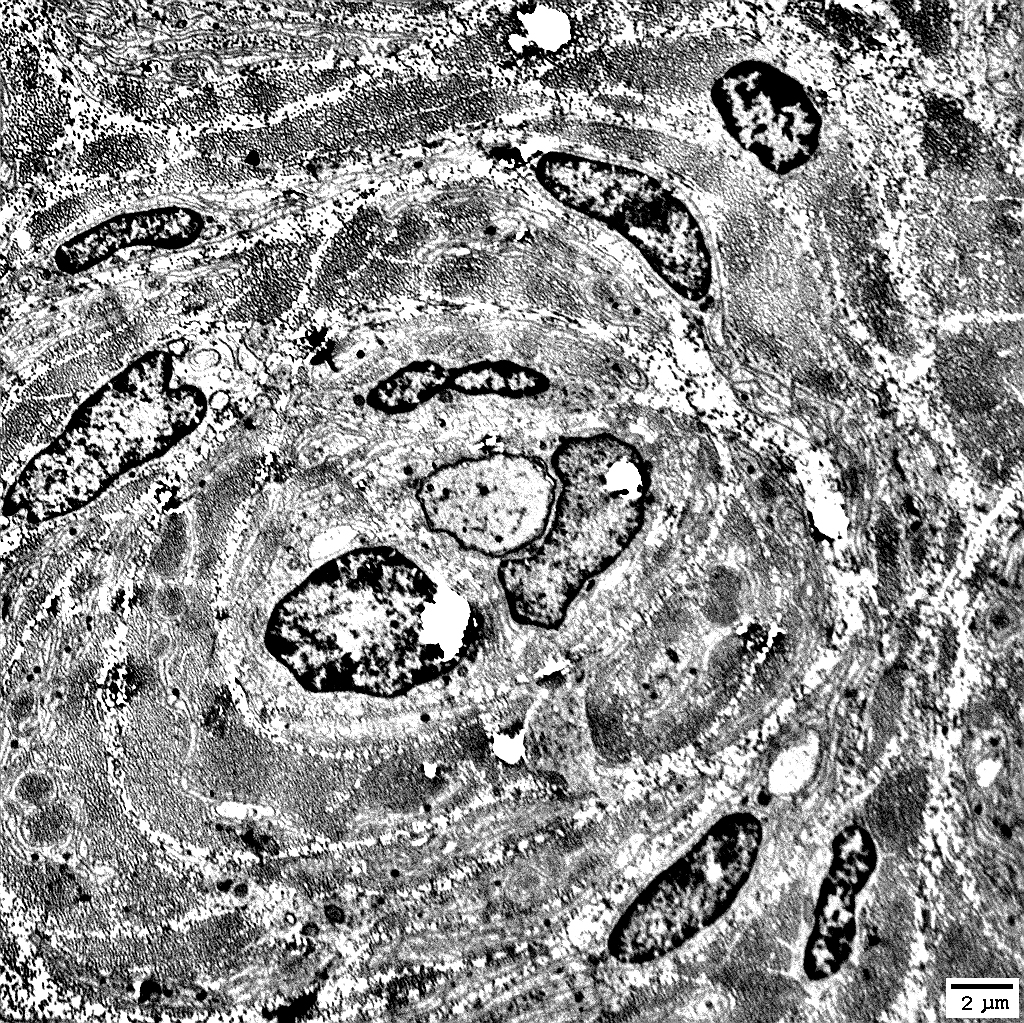

Onion Bulbs

Some contain myelinated axons; Others are empty (

"Obsolete")

Contain abundant

non-myelinating Schwann cells

Non-myelinating Schwann cells in onion bulbs: In layers